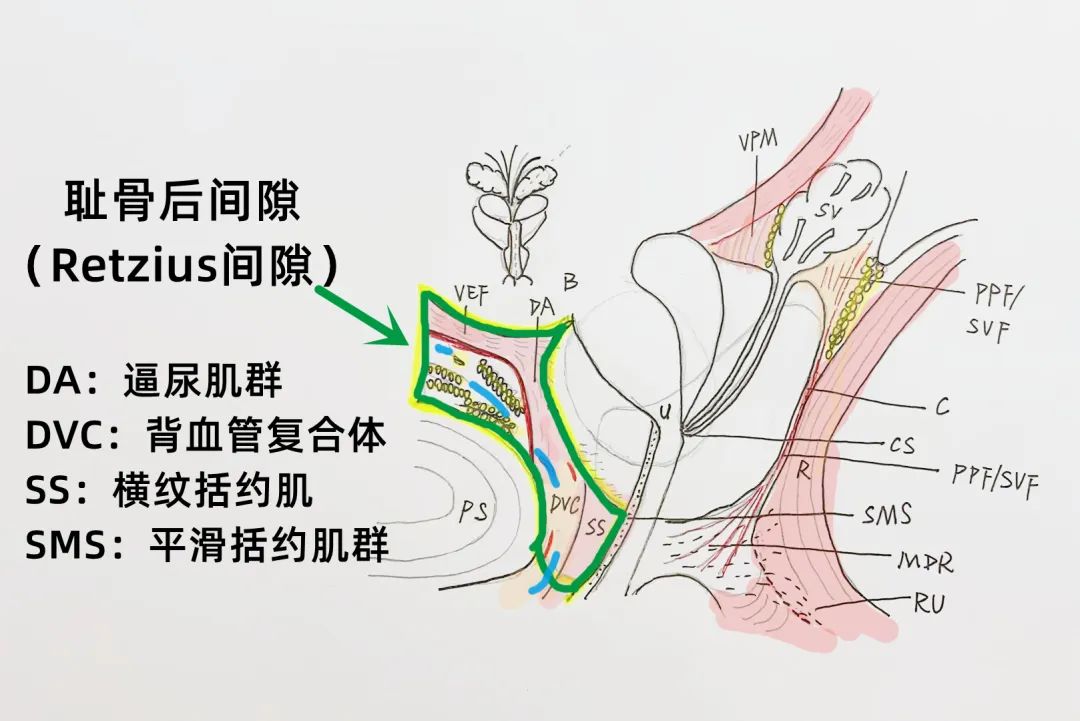

马利民、成兵团队术前依据患者的前列腺MR结果精准定位病灶,围绕病灶勾画出布针靶区,结合了超声的实时性和MR的高对比度的优势,术中根据术前已画出的病灶范围精心实施布针方案,大大减少了手术时长。

布针结束后依次在各组不可逆电穿孔针之间通电,第一个循环电场设置为1500v/cm,脉冲数为150个,第二个循环电场设置为100v/cm,脉冲数为100个。经过35分钟不可逆电穿孔消融,华东地区首例多模态AI影像融合下前列腺癌“不可逆电穿孔”消融术顺利结束。